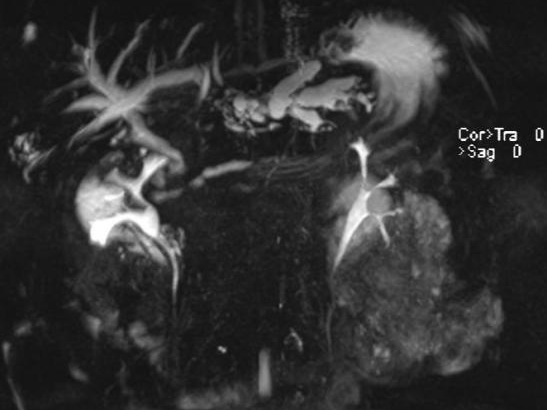

结果检查一看:患者肝内胆管存在多发结石并伴有胆管扩张。由于结石长期在体内“作祟”,引发了局部组织的严重炎症和破溃,最终导致肝脏穿孔,并与腹壁形成了一条异常的“窦道”(瘘管)。这条通道使得肝脏内的感染物直接穿出腹壁,造成了腹壁流脓的危重局面。

张继红教授带领手术团队沉着应对、精准操作,小心翼翼地层层分离粘连组织,逐步梳理紊乱的解剖结构,最终发现肝左叶与腹壁之间形成了约1cm宽的致密瘘管,管内可见少量白色分泌物,正是这处“漏点”导致患者腹壁反复流脓。在精准保护周围肠管、重要血管不受损伤的前提下,团队成功切除病变的左半肝,彻底清除病灶。

术后解剖离体肝脏标本发现,患者肝内胆管扩张明显,内有多发褐色结石,最大直径达1×1cm,这些结石长期反复刺激胆管壁,正是引发肝脏穿孔、腹壁流脓的根本原因。